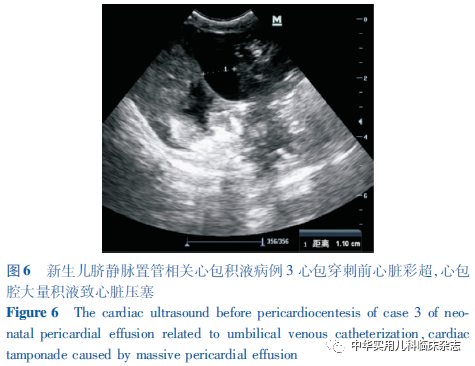

病例资料1.1 病例1 患儿,男,胎龄33+4周,第2胎,第3产,出生体重2 150 g,Apgar评分1 min 8分,5 min 9分,出生后因“早产、呼吸费力10 min”,以新生儿呼吸窘迫综合征(NRDS)收入武汉大学中南医院妇儿医院儿科NICU。入院后予经鼻持续气道正压通气(nCPAP),出生后10 h予UVC(法国美德 PRODIMED 3.5F),过程顺利,置管深度采用Shukla公式计算(1.5×出生体重+5.6+脐带残端长度)[2],床旁X线示导管尖端位于胸椎T8水平。出生后34 h患儿出现血氧饱和度(SpO2)、心率(HR)及血压(BP)下降,肤色苍灰、发花,呼吸节律慢,心音微弱,立即行气管插管及复苏囊正压通气,SpO2缓慢回升,但HR仍持续下降,予生理盐水扩容、肾上腺素强心、碳酸氢钠纠酸及持续心肺复苏,效果不佳。急行床旁彩超提示心包腔大量液性暗区(图1),立即行心包穿刺及闭式引流,术后患儿生命体征逐渐平稳,连续2 d复查彩超均未显示心包积液,复查胸片见UVC导管尖端上移至胸椎T6水平(图2),遂予拔除。心包积液送检结果提示:葡萄糖69.24 mmol/L,乳糜实验阴性,细菌培养阴性,与当天输注的不含脂肪乳静脉营养液成分相符,考虑心包积液主要为经UVC渗漏的静脉营养液。患儿住院治疗24 d出院,目前10月龄,生长发育良好,无心血管及神经系统后遗症。1.2 病例2 患儿,男,胎龄31周,第3胎,第2产,出生体重1 830 g,Apgar评分1 min 7分, 5 min 8分, 10 min 7分,经新生儿复苏后以NRDS收入院。入院后给予气管插管、肺表面活性物质(PS)气管内注入后行呼吸机辅助通气。出生后8 h顺利行UVC置入, 床旁X线定位导管尖端于胸椎T8水平。出生后第2天,患儿于呼吸机支持下仍可见呼吸窘迫表现,予第2剂PS气管内注入。同日夜间,患儿突发SpO2持续下降,肤色苍灰、发花,四肢冰冷,呼吸节律慢,心音低钝、遥远,立即心肺复苏并予扩容、纠酸、利尿及肾上腺素强心等处理,患儿心音仍低钝,肤色仍灰,且气管导管内可见鲜血涌出。急行床旁心脏彩超提示心包腔大量积液(图3),胸片提示UVC尖端移位至T5~T6,心影增大(图4A),立即拔除UVC并行心包穿刺引流术,抽出淡黄色乳糜样液体约20 mL,术后患儿生命体征渐平稳,肺出血停止。术后第1-3天多次复查心脏彩超均未见心包积液,复查胸片见心影较前缩小(图4B)。心包积液送检结果提示:葡萄糖88.66 mmol/L,乳糜实验阳性,细菌培养阴性,与当天输注的含脂肪乳静脉营养液成分相符。此后患儿由于支气管肺发育不良等早产儿常见疾病继续治疗,共住院47 d出院。患儿目前9月龄余,生长发育良好,无心血管及神经系统后遗症。1.3 病例3 患儿,男,胎龄27+6周,第2胎,第2产,因其母“重度先兆子痫;抗磷脂综合征高同型半胱氨酸血症、黑尔普综合征”剖宫产娩出,出生体重850 g,Apgar评分1 min 5分,5 min 6分,10 min 7分,经新生儿复苏后,携气管插管于T组合通气下转入院。入院后予PS气管内注入及高频呼吸机辅助通气。出生后2 h 行UVC置入,行床旁X线检查示导管尖端位于胸椎T9水平。出生后第1天复查胸片见UVC尖端移至T5水平(图5A),予外拔1.5 cm使之回至T9水平。出生后第5天,患儿于双相气道正压通气下,出现明显呼吸困难,遂再次行气管插管及呼吸机支持。同日夜间患儿突发全身发绀,气管导管内可见鲜血,SpO2、HR、BP无法测出,听诊双肺呼吸音低,心音极其微弱、遥远,立即行心肺复苏,予肾上腺素强心、碳酸氢钠纠酸、生理盐水扩容,患儿症状无改善。急诊床旁胸片见心影明显增大(图5B),彩超提示心包积液(图6)、右侧胸腔积液,立即行心包及胸腔穿刺,抽出乳糜样混浊液体共20 mL后复查彩超未见明显心包及胸腔积液。持续心肺复苏、液体复苏及间断电除颤,患儿自主呼吸及HR仍未恢复,抢救持续约3 h后宣告临床死亡。